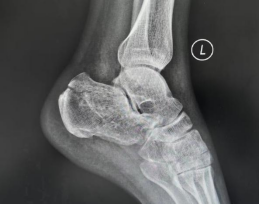

案例1:患者42岁,因高坠伤致左跟骨骨折、伴活动受限9小时入院。入院诊断:左跟骨骨折。入院后,科室采用3D打印导板辅助下行经皮跟骨骨折闭合复位内固定术,通过导入患者跟骨CT数据完成三维重建,在计算机上进行虚拟复位并精准规划出用于固定骨折块的最佳“虚拟螺钉”路径的进针点、角度及深度,以安全地穿过骨折块并达到最大把持力;再将计算机中的“虚拟路径”转移到患者体表,依据规划好的钉道,生成一个能与患者足跟外侧皮肤及骨骼解剖标志(如跟骨结节、腓骨远端等)完美贴合的个性化手术导板。术中只需将灭菌后的个性化导板准确贴合在患者足跟外侧预定的皮肤位置,借助导板导向孔直接钻入导针,实现了置钉精准化、手术微创化与效率提升的多重目标,最大程度保护了局部软组织血运,降低了伤口并发症风险。